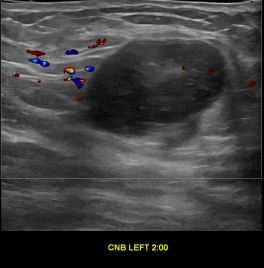

상기환자는 좌측 만져지는 멍우리 있어 검사위해 내원하신 30대 후반

여성분으로 의심스러운 좌측유방혹 조직검사 시행해 유방암으로 진단되었습니다